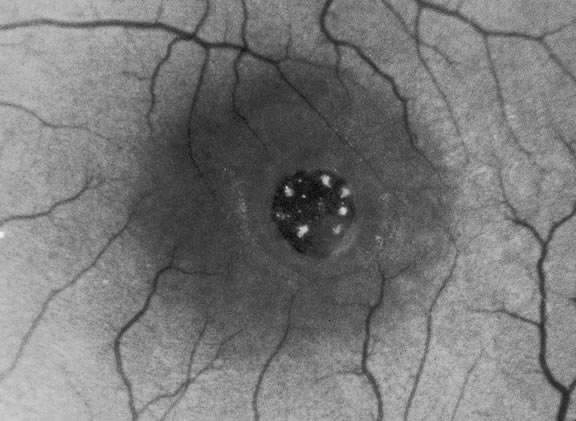

The mechanical relationship between the vitreous and the retina is mediated by the posterior vitreous cortex, which is also called the posterior hyaloid. The posterior vitreous cortex consists of relatively densely packed type II collagen fibrils arranged tangentially to the retina. The retinal basal lamina is the basement membrane of the Müller's cells that comprise the internal limiting membrane (ILM) of the retina.6,7 Ultrastructurally, the ILM consists of three layers.8 Adjacent to the end feet of the Müller's cells is the lamina rara interna. The lamina rara externa is contiguous with the vitreous cortex. In between these layers is the lamina densa. Collagen fibers of cortical vitreous are tangential to the lamina rara externa. The ILM is composed of primarily type IV collagen but also contains fibronectin, laminin, and type I collagen.9 The morphology of the ILM varies topographically in the retina. The ILM, and in particular the lamina densa, is thin in the retinal periphery and becomes increasingly thicker and irregular in the posterior retina.6,8

The ILM thickens from 50 nm at the vitreous base to 300 nm at the equator to 1900 nm posteriorly. In the foveal region the ILM thins to 10 to 20 nm.10

The nature of the adhesion between the vitreous cortex and the ILM is enigmatic. This adhesion is strongest at the optic nerve, the macula, the vitreous base, and retinal vessels. Foos6 demonstrated attachment plaques between Müller's cell cytoplasm and the ILM in the basal and equatorial retina (Fig. 2). Vitreous traction mediated by vitreous fibrils may contribute to these adhesions. These attachment plaques are not present posterior to the equator except where the ILM is thinned in the fovea. This anatomic variation in the fovea region may play a role in the pathogenesis of some of the vitreomacular disorders.